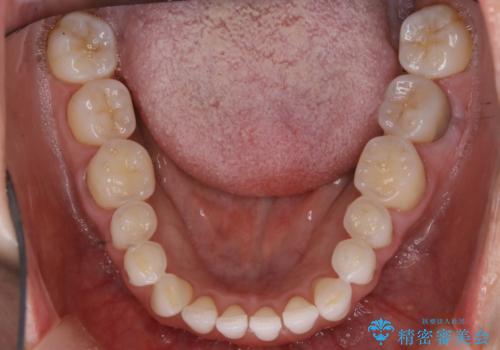

【非抜歯】マウスピースでオープンバイトを治す

- 歯ぎしりや食いしばり、噛み合わせの治療とガタつきを治したいとのことでご来院されました。

検査の結果、前歯と臼歯の高さに差があり、前歯が全く当たらない状態になっているため歯ぎしりによって奥歯が削れてしまっているという状態でした。

マウスピースの矯正装置を用い、ガタつきを治しつつ奥歯を沈めていくことで噛み合わせ全体の改善を図りました。